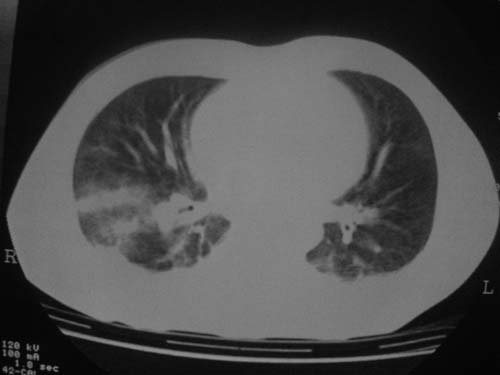

外伤病人,年龄忘了,中年人右侧肋骨骨折了,

这是刚住院拍的片子。